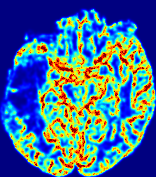

LesionRefer to captionRefer to captionRefer to captionRefer to captionRefer to captionRefer to caption𝐕rgbsubscript𝐕𝑟𝑔𝑏{\bf{V}}_{rgb}Refer to captionRefer to captionRefer to captionRefer to captionRefer to captionRefer to caption𝐕2subscriptnorm𝐕2{\|\bf{V}}\|_{2}Refer to captionRefer to captionRefer to captionRefer to captionRefer to captionRefer to captionRefer to caption3.53.53.52.82.82.82.12.12.11.41.41.40.70.70.70.00.00.0(mm/s)𝑚𝑚𝑠(mm/s)D𝐷DRefer to captionRefer to captionRefer to captionRefer to captionRefer to captionRefer to captionRefer to caption0.0200.0200.0200.0160.0160.0160.0120.0120.0120.0080.0080.0080.0040.0040.0040.0000.0000.000(mm2/s)𝑚superscript𝑚2𝑠(mm^{2}/s)Slice #1Slice #2Slice #3Slice #4Slice #5Slice #6

Figure 4: PIANO feature maps for another patient in the ISLES 2017 training set, where the lesion is located in the right hemisphere. Top row: segmented stroke lesion region (white) on different slices. The corresponding slices for the PIANO feature maps are shown in the following rows.

For a better insight into an estimated velocity field 𝐕𝐕{\bf{V}} and diffusion field 𝐃𝐃{\bf{D}}, we compute the following maps: (1) 𝐕rgbsubscript𝐕𝑟𝑔𝑏{\bf{V}}_{rgb}: Color-coded orientation map of 𝐕=(Vx,Vy,Vz)T𝐕superscriptsuperscript𝑉𝑥superscript𝑉𝑦superscript𝑉𝑧𝑇{\bf{V}}=(V^{x},V^{y},V^{z})^{T}, obtained by normalizing 𝐕𝐕{\bf{V}} to unit length and mapping its 3 components to red, green, blue respectively; (2) 𝐕2subscriptnorm𝐕2\|{\bf{V}}\|_{2}: 222 norm of 𝐕𝐕{\bf{V}}; (3) D𝐷D: scalar field in Eq. 5.

Fig. 3 and Fig. 4 show the PIANO feature maps estimated from two ISLES 2017 patients: all are highly consistent with the lesion in both cases. Details of the blood flow trajectories are revealed in 𝐕rgbsubscript𝐕𝑟𝑔𝑏{\bf{V}}_{rgb} by the ridged patterns and the sharp changes of colors in the unaffected (right) hemisphere, while the flat patterns appearing within the lesion provide little directional information about the velocity and indicate low velocity magnitudes. Velocity magnitudes are more directly visualized via 𝐕2subscriptnorm𝐕2\|{\bf{V}}\|_{2}, from which one can easily locate the lesion where 𝐕2subscriptnorm𝐕2\|{\bf{V}}\|_{2} is low. D𝐷D also indicates lower diffusion values in the lesion, though with less contrast potentially due to the fact that it captures the accumulated effect of CA diffusion at the voxel-level.